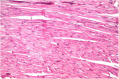

The carotenoid rich fraction of microalgae Dunaliella salina (crf-DS) have been receiving great attention, due to they abilities to protect and improve various disorders. The objective of this study is to explore the therapeutic efficiency of crf-DS on obesity-assciated cardiac dysfunction in the high-fat diet (HFD) treated rats. These rats were orally administered with crf-DS (150 mg /kg body weight), for six consecutive weeks in comparison with reference drug(orlistat) VSports手机版. Specific cardiac biomarkers were examined including; adiponectin, plasminogen activator inhibitor (PAI-1), glucagon, troponin-I (cTnI). The cell adhesion molecules (VCAM and ICAM), C-reactive protein (CRP), collagen type II (Col II), collagen alpha-1 (III) chain (Col3A1), lipoxygenase activity (LOX), as well as histopathological examination of cardiac tissue were investigated. Results indicated a significant reduction(P ≤ 0. 05) in adiponectin and glucagon levels in serum of obese rats. However, cTnI, PAI-1, cell adhesion molecules, CRP, Col II, and Col3A1 and LOX levels declared marked increase. Histopathological examination of cardiac tissue showed fibrosis with severe congestion in the myocardial blood vessels. On the other hand, rats medicated with a crf-DS demonstrated noticeable ameliorating effect in all the measured parameters. Beside, myocardial tissue of obese rats showed no alteration. Hence, It could be concluded that, oral supplementation with crf-DS is able to attenuate cardiac dysfunction in obese rats. Further extended work is needed to exploit, the possible application of D. salina as nutraceuticals and food additives. .